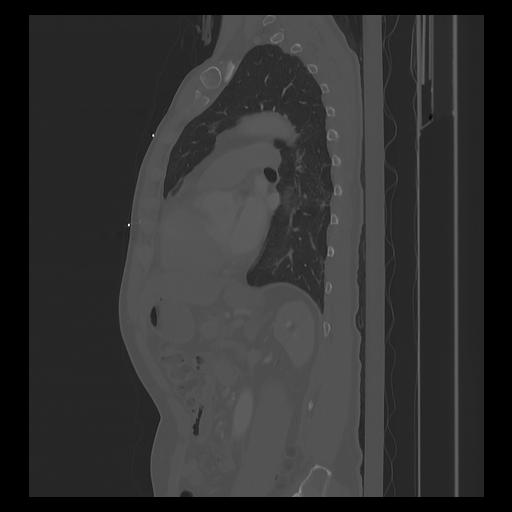

33 PULMON,CE,Sagittal,3.000,PULMON,Sagittal,